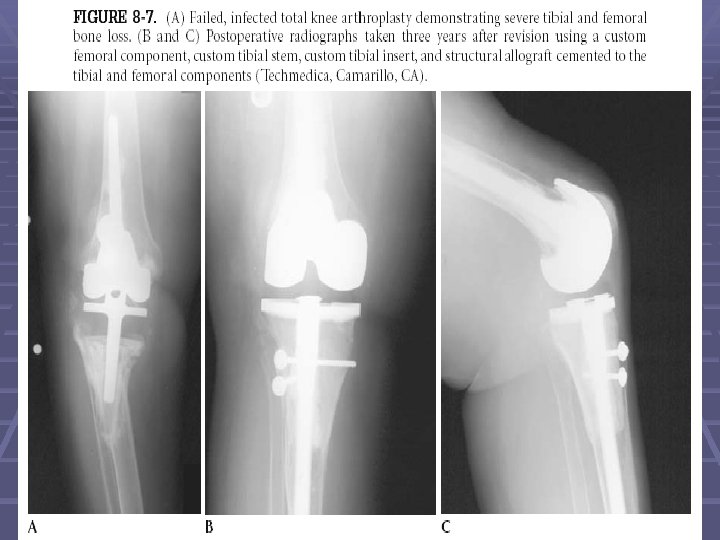

The Tibial Prep. Cont. § Rarely, a custom tibial component or a proximal tibial allograft may be necessary because of extensive bone loss

Pre and Post op.